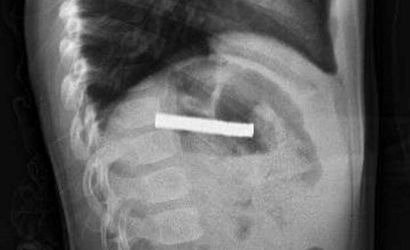

Fırat Üniversitesi Çocuk Gastroenteroloji Hepatoloji ve Beslenme Bilim Dalı Başkanı Prof. Dr. Yaşar Doğan liderliğindeki ekip, yaptığı tetkiklerde mıknatısların yemek borusunda yapışarak tıkanmaya neden olduğunu belirledi. Ekip, müdahale ederek mıknatısları başarılı bir biçimde çıkardı.

Çocuk, yapılan işlemin ardından gözlem altında tutuldu ve ailesinin isteğiyle taburcu edildi. Prof. Dr. Yaşar Doğan, "Mıknatıslar uzun süre yemek borusunda kaldığı için hasar bırakmıştı. İşlemi kolaylaştırmak için mıknatıslar mideye alındı ve mideden özel bir fileyle çıkarıldı" şeklinde bilgi verdi.